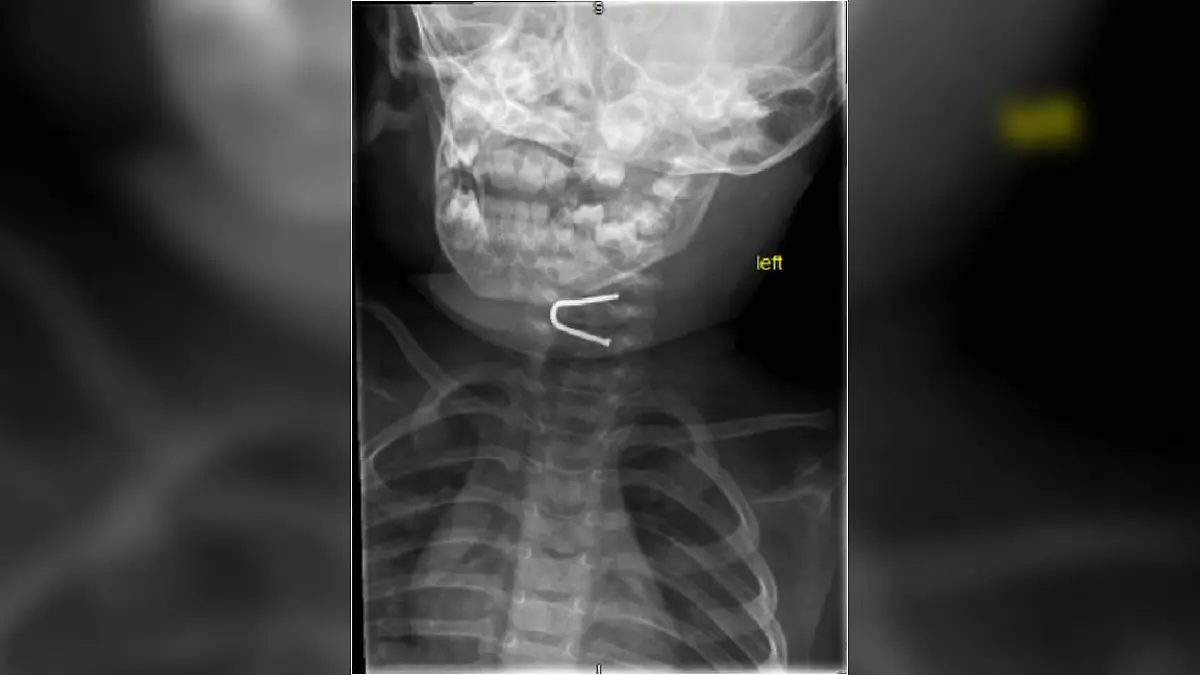

Hätten die Eltern nicht gesehen, dass das Kind etwas verschluckt, wäre der Nagel unentdeckt geblieben. Erst eine Röntgenaufnahme des Brustkorbs habe das „Objekt in Form eines ‘U’“ in der Speiseröhre gezeigt.

Am Ende musste ein Team von HNO-Ärzten und Gastroenterolgen anrücken, um den Nagel gefahrlos aus der Speiseröhre des Babys zu entfernen. Der hatte sich nämlich etwas verkeilt und steckte fest. Glücklicherweise ist der Eingriff problemlos verlaufen und das Baby erholt sich gut.